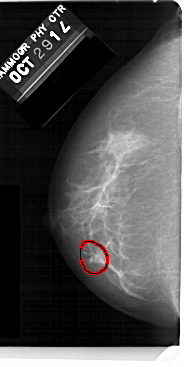

A_1477_1.LEFT_MLO

FILE: A_1477_1.LEFT_MLO.OVERLAY

TOTAL_ABNORMALITIES 1

ABNORMALITY 1

LESION_TYPE CALCIFICATION TYPE AMORPHOUS DISTRIBUTION CLUSTERED

ASSESSMENT 4

SUBTLETY 3

PATHOLOGY BENIGN

TOTAL_OUTLINES 1

BOUNDARY